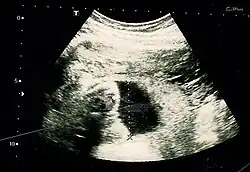

Obstetric ultrasonography is routinely used for dating the gestational age of a pregnancy from the size of the fetus, determine the number of fetuses and placentae, evaluate for an ectopic pregnancy and first trimester bleeding, the most accurate dating being in first trimester before the growth of the foetus has been significantly influenced by other factors.[22] Ultrasound is also used for detecting congenital anomalies (or other foetal anomalies) and determining the biophysical profiles (BPP), which are generally easier to detect in the second trimester when the foetal structures are larger and more developed.[23]

X-rays and computerized tomography (CT) are not used, especially in the first trimester, due to the ionizing radiation, which has teratogenic effects on the foetus.[24] No effects of magnetic resonance imaging (MRI) on the foetus have been demonstrated,[25] but this technique is too expensive for routine observation. Instead, obstetric ultrasonography is the imaging method of choice in the first trimester and throughout the pregnancy, because it emits no radiation, is portable, and allows for realtime imaging.[26]

The safety of frequent ultrasound scanning has not been confirmed. Despite this, increasing numbers of women are choosing to have additional scans for no medical purpose, such as gender scans, 3D and 4D scans.[27] A normal gestation would reveal a gestational sac, yolk sac, and fetal pole.[28]

The gestational age can be assessed by evaluating the mean gestational sac diameter (MGD) before week 6, and the crown-rump length after week 6. Multiple gestation is evaluated by the number of placentae and amniotic sacs present.[29]